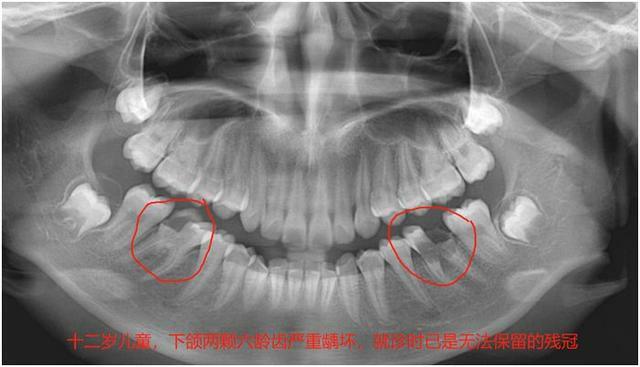

*十二歲(替牙期結束)

十二歲左右,孩子口腔內的乳牙會全部脫落,28顆恆牙全部萌出(智齒要18歲以後長),此時正是孩子的發育高峰期,也是兒童牙齒矯正的最佳時機。

家長們若是發現自己家的孩子牙齒不齊,若是骨性的,儘量在十歲之前做干預性處理,若是單純的牙齒不齊,就等到孩子12歲換完牙齒後再做矯正。